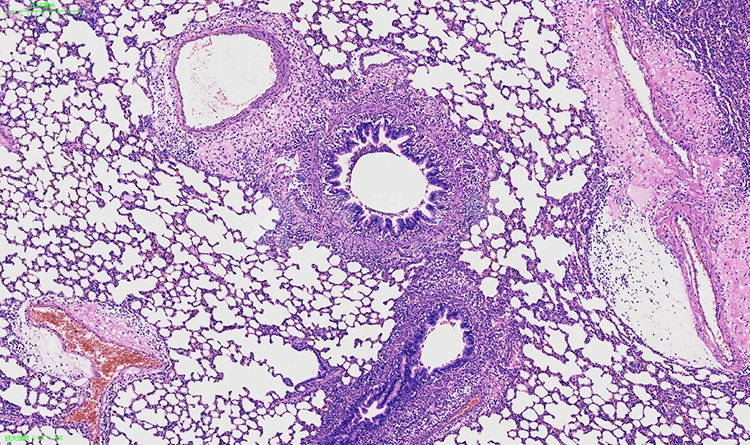

冰冻切片和染色是病理学检测中常用的技术手段,用于研究组织和细胞的结构、功能以及病变情况。以下将介绍冰冻切片和染色在病理学检测中的意义、应用方法以及对疾病诊断和研究的影响。

冰冻切片和染色在病理学检测中的意义重大。通过冰冻切片,可以快速地获取新鲜组织样本,并保留其原有的形态结构和细胞活性,为进一步的组织学观察提供了良好的基础。而染色则能够突出组织和细胞的特定结构和成分,使其更易于观察和分析。冰冻切片与染色相结合,可以为医生和研究人员提供丰富的信息,帮助他们诊断疾病、评估治疗效果以及进行病理学研究。

关于染色方法,常用的染色技术包括常规的血液染色(如伊红染色、嗜酸性染色等)、组织结构染色(如苏木精-伊红染色、伊红-金黄染色等)以及特殊染色(如免疫组化染色、核酸染色等)。这些染色方法能够使细胞和组织的结构、功能以及病变情况更加清晰可见,有助于对疾病进行定性和定量的分析。

综上所述,冰冻切片与染色在病理学检测中起着重要作用。它们能够提供新鲜组织样本的形态结构信息和细胞活性,帮助医生进行疾病诊断和治疗评估,同时也支持病理学研究的推进。通过冰冻切片和染色技术的应用,我们可以更加全面地了解疾病的发生机制和病理变化,为临床诊断和医学研究提供有力支持。